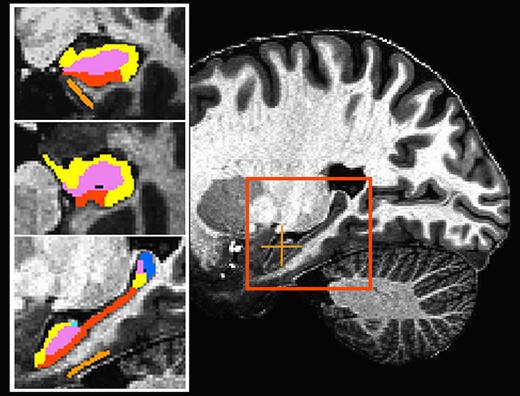

La cartographie IRM à ultra-haut champ pour cartographier le cerveau des personnes atteintes trisomie 21 (T21) a permis à des chercheurs de la Case Western Reserve University, de la Cleveland Clinic et autres institutions universitaires de détecter des différences subtiles dans la structure et la fonction de l'hippocampe, région cérébrale liée à la mémoire et à l'apprentissage.

Dans une étude publiée dans la Revue Brain Communications, une cartographie si détaillée a ainsi permis à l'équipe de chercheurs de mieux comprendre comment chaque sous-région de l'hippocampe chez les personnes atteintes de T21 est fonctionnellement connectée à d'autres parties du cerveau. « Le but ultime de cette approche est d'avoir une technique objective pour compléter les évaluations neuropsychologiques afin de mesurer les compétences fonctionnelles des personnes atteintes de T21 », précise le Pr Alberto Costa, Professeur de pédiatrie et de psychiatrie à la Case Western Reserve University School of Medicine et auteur principal de l’étude.

L’IRM 7T est de plus en plus disponible pour la recherche humaine, permettant aux neuroscientifiques de cartographier le cerveau à une résolution plus élevée sans perdre de qualité de l'image. Pour mener leur étude, les chercheurs ont effectué une première comparaison in vivo des volumes de différents segments anatomiques de l'hippocampe entre des personnes atteintes de T21 et des individus témoins du même âge et du même sexe.

Pour chaque participant, des cartographies de connectivité fonctionnelle du cerveau entier ont été créées pour l'hippocampe gauche et droit. « Les gains de sensibilité et de résolution d'image réalisables avec l'IRM à ultra-haut champ fournissent des niveaux de détail et de précision qui n'étaient pas accessibles auparavant dans les études sur des personnes vivantes et non sédatées, atteintes du syndrome de Down », remarque le Pr Katherine Koenig, Professeure adjointe de radiologie à la Cleveland Clinic Lerner College of Medicine de la Case Western Reserve University et co-auteur de l'étude.